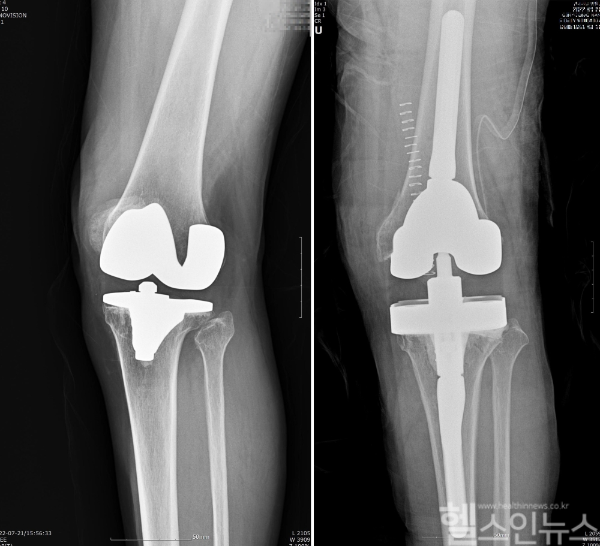

인공관절 역시 무릎 관절처럼 생활 습관에 따라 시간이 지날수록 점차 마모된다. 이런 경우 새로운 인공관절을 끼워 넣는 ‘인공관절 재치환술’을 고려해봐야 한다. 오래된 인공관절이 닳아서 흔들리거나 염증 등 문제가 발생했을 때 시행하며 이 경우 무릎 주변에 통증, 발열을 느끼고 소리도 날 수 있다.

인공관절 재치환술은 새 인공관절을 넣기만 하면 되는 간단한 수술일 것 같지만 의외로 까다롭다. 가장 먼저 고려해야 할 점은 인공관절 재치환술이 필요한 환자가 대부분의 경우 고령이라는 것이다. 합병증을 동반한 이가 많고 또 환부 주위가 염증 등으로 손실된 경우가 흔하다. 본원 통계에 따르면 인공관절 재수술 환자 809명 중 80세 이상이 16%를 차지했다.